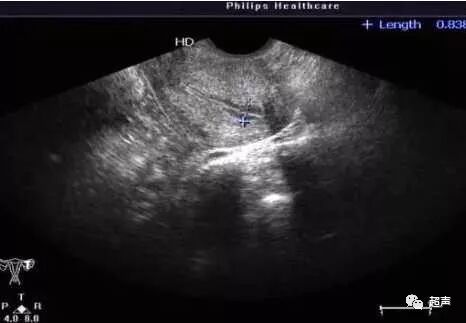

C型内膜常见于黄体期(即排卵后到下次月经来潮前),厚度约10-14mm。为均质强回声,无宫腔中线回声。

C型内膜